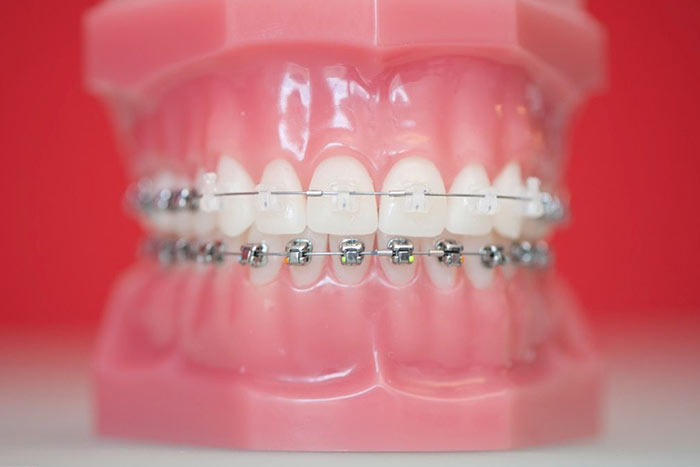

Ästhetikbrackets

kleine Dimension - erleichterte Zahnpflege

Klappenmechanismus - weniger Reibung, kleinere Kräfte, zügige Behandlung

Wir verwenden in unserer Praxis selbstligierende Keramikbrackets.

Diese Systeme stellen einen optimalen Kompromiss aus Ästhetik, Funktion und Komfort dar. Die Kontrollintervalle liegen zwischen 6 und 8 Wochen. Die Zwischenräume lassen sich gut reinigen. Verfärbungen treten so gut wie nicht auf.